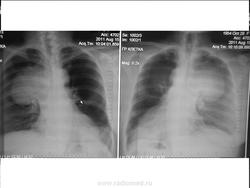

Загадочные кистовидные образования.

Жалобы на одышку. Архив 6 мес назад без данных изменений. Из анамнеза Са МЖ.

За 6 месяцев это не могло вырасти...Что это? Что-то из средостения?

1.  Mts (но лично мне пока еще не встречались mts таких размеров из МЖ, больше похоже на из ЖКТ)

2. Паразитарные кисты (если учитывать появление в течение 6 мес.)

Метастазы, как по мне....возникновение и рост метастазов находится под значительным влиянием эндогенных факторов. Молодой возраст, гормональные сдвиги в сторону гиперэстринизма, беременность и лактация, а возможно и нейротрофические влияния способствуют развитию метастазов. Несомненную роль в ускорении появления и роста метастазов могут оказать и экзогенные факторы: травма опухоли при массаже и неполноценной операции, ультрафиолетовое облучение и неоправданно длительное введение эстрогенных препаратов.....

Такую картинку могла дать и саркома лёгкого, но не за 5 месяцев. На мой взгляд, имела место "хрень" с архивом, или перепутали, или аналогичное...

на саркому можно было бы подумать.если бы не было такого же шарика в S9-10 cлева. А тень-"полутень" слева в в\поле более мягкой по интенсивности выглядит потому,что  и снимок с разворотом (и левое легкое чернее) и общее равномерное снижение пневматизации легочной ткани правого легкого- что-то (mts?) мешает норм. вентиляции на уровне правого главного бронха.

Саркома может быть и из нескольких "шариков"...не забывайте об этом...

из нескольких возможно, а когда они не связаны между собой ( в данном случае в средостении и слева в н\легочном поле) тоже о саркоме думать?

Тогда - абсцессах...ведь тенеобразований как минимум - два...и мне не дает покоя и третья тень, на которую указывал Валентин Львович....